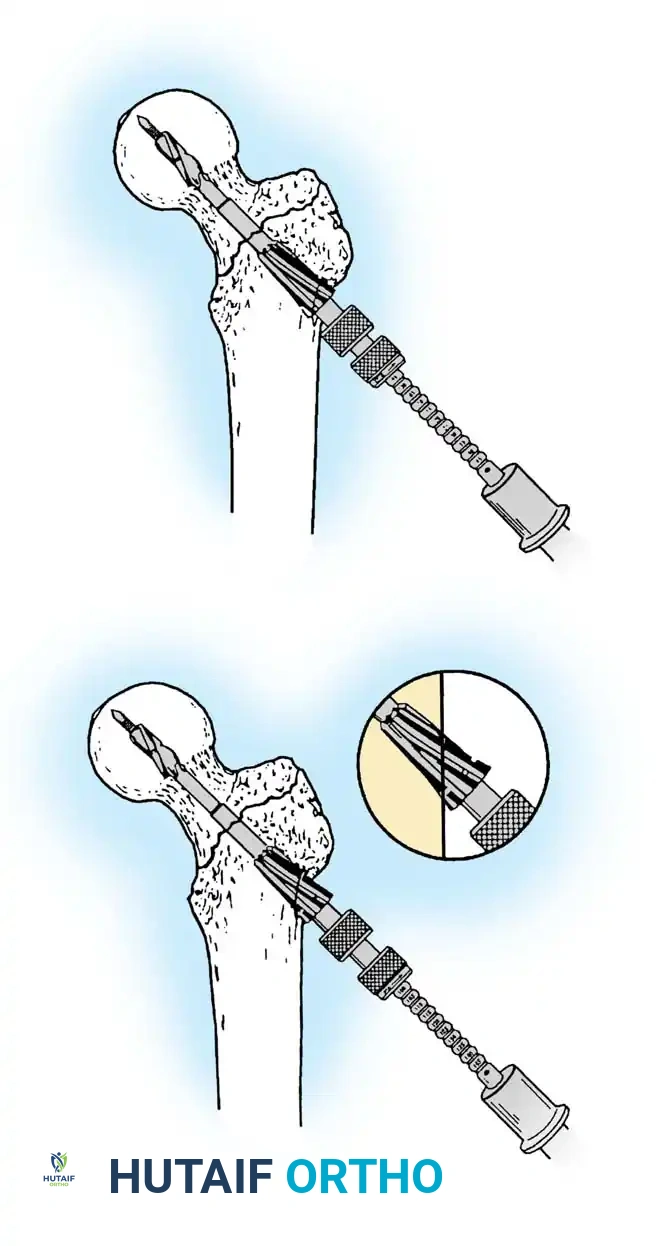

3. Guide Wire Placement

Whether using an SHS or a CMN, accurate placement of the guide wire into the femoral head is the most critical step of the operation.

Insertion of the guide wire. The wire must be positioned centrally in the femoral head on both AP and lateral views.

The Tip-Apex Distance (TAD):

Described by Baumgaertner, the TAD is the sum of the distance from the tip of the lag screw to the apex of the femoral head on both the AP and lateral radiographs. A TAD of less than 25 mm is strongly predictive of successful fixation; a TAD > 25 mm significantly increases the risk of screw cut-out.

4. Reaming and Lag Screw Insertion

Once the guide wire is perfectly positioned, the lateral cortex is opened, and the femoral neck is reamed over the wire.

Reaming of the femoral neck and head over the precisely placed guide wire, preparing the channel for the lag screw.

The lag screw is then inserted. It is crucial not to over-insert the screw, which can penetrate the articular cartilage, nor to under-insert it, which compromises fixation.

5. Intramedullary Nailing (For Unstable Fractures)

If a cephalomedullary nail is chosen, the entry point is established at the tip of the greater trochanter (or slightly medial, depending on the specific implant design).

Insertion of the cephalomedullary nail down the femoral shaft. Care must be taken not to distract the fracture site during insertion.

After the nail is seated, the proximal lag screw(s) are inserted through the nail into the femoral head, adhering to the same TAD principles.

Proximal locking of the cephalomedullary nail. The targeting guide ensures accurate trajectory into the femoral neck.

Finally, distal locking screws are placed to control rotation and maintain length.